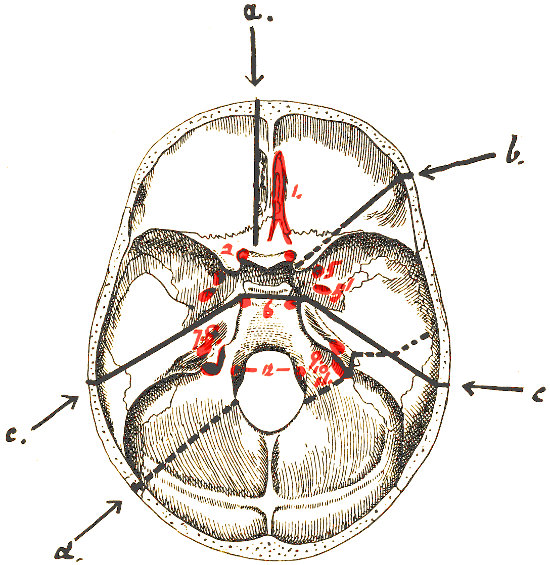

Fig. 2. Cranio-cerebral Topography. 1, 1, Reid’s base-line; 2, 2, A line parallel to the above at the level of the supra-orbital margin; 3, The middle meningeal artery; 4, The anterior branch; 5, 5, 5, The three sites for trephining; 6, The posterior branch; 7, The site for trephining; 8, The point for trephining to reach the descending horn of the lateral ventricle; 9, The lateral sinus; 10, The inion; 11, The mastoid process; 12, Macewen’s suprameatal triangle; 12a, The mastoid antrum; 12b, The facial nerve; 13, The suprameatal and supramastoid crests; 14, 14, The temporal crest; 15, The temporal fossa; 16, The external angular frontal process; 17, The tendo-oculi attachment; 18, The lachrymal groove. (Reproduced, by the permission of Mr. H. K. Lewis, from the author’s work on ‘Landmarks and Surface-markings’.)

This artery is given off from the internal maxillary; after a short extra-cranial course it enters the skull through the foramen spinosum, and soon divides into two main terminal branches. The site of division corresponds to a point situated just above the centre of the zygoma.

The anterior branch passes at first in a forward and upward direction towards the anterior inferior angle of the parietal bone, and then turns upwards and backwards towards the vertex of the skull. The main ‘danger zone’ in the course of this vessel may be mapped out by taking points which lie respectively 1, 11⁄2, and 2 inches behind the external angular frontal process and an equal distance above the upper border of the zygoma. A line uniting these three points represents that part of the anterior division of the middle meningeal artery which is most liable to injury and which therefore most frequently requires exposure.

The uppermost point may, however, be regarded as the ‘site of election’ for exposure of the artery, as, in trephining over either of the two lower points, difficulty may be experienced in the removal of the disk of bone, since the posterior border of the great wing of the sphenoid tails off on to the anterior inferior angle of the parietal bone in such a manner that to effect a clean removal of the disk is often impossible. Another disadvantage to trephining low down lies in the fact that in about 30 to 40 per cent. of cases the artery occupies, in that situation, a canal in the bone.

The posterior branch passes almost horizontally backwards, parallel to the zygoma and supramastoid crest, towards the posterior inferior angle of the parietal bone. The vessel can readily be exposed[6] by trephining over the point at which a line drawn backwards from the upper border of the orbit, parallel to Reid’s base-line,[1] cuts another line directed vertically upwards from the posterior border of the mastoid process.

Both branches of the middle meningeal artery possess important relations to the cortex cerebri, the anterior branch passing upwards in relation to the precentral or motor area, traversing, from below upwards, the motor speech area (on the left side of the head), the centres for the movements of the face, upper extremity, trunk, and lower extremity. The posterior branch, on the other hand, passes backwards in relation to the temporo-sphenoidal lobe, one of the so-called ‘silent areas’ of the brain. Throughout their course the middle meningeal vessels lie between the dura mater and the bone.

The lower limit of the cerebrum can be mapped out in the following manner: From a point situated about 1⁄2 inch above the nasion a line is drawn outwards which follows the curve of the upper border of the orbit as far as the external angular frontal process, thence curving upwards and backwards to the Sylvian point (see below). The temporo-sphenoidal lobe sweeps forwards to the posterior border of the malar bone, and its lower limit lies practically flush with the upper margin of the zygoma. At and behind the ear the lower limit of the cerebrum corresponds to the suprameatal and supramastoid crests, subsequently following the curve of the lateral sinus from the mastoid process to the external occipital protuberance.

The Sylvian point represents the site of divergence of the three limbs of the Sylvian fissure. It lies 11⁄4 inches behind the malar tubercle and 11⁄2 inches above the upper border of the zygoma. The main posterior horizontal limb passes backwards and upwards to a second point situated 3⁄4 inch below the parietal prominence.

The vertical limb is directed upwards for about 1 inch, whilst the anterior horizontal limb passes forwards for about the same distance.

This, from a surgical point of view,[7] the most important fissure of the brain, is represented as follows: A point is taken in the median antero-posterior line which lies 1⁄2 inch behind the mid-point between nasion and inion, and from this point a line is drawn, for 31⁄2 to 4 inches, towards the mid-point of the zygoma. This line is inclined to the median antero-posterior line at an angle of 671⁄2° (three-quarters of a right angle).

In the representation of these two fissures, two points require to be determined—the malar tubercle and the lambda. Allusion has already been made to the former; the latter is usually readily located as the point of intersection of the sagittal and lambdoid sutures. A line uniting these two points corresponds in its middle third to the temporo-sphenoidal fissure, and in its posterior inch or so to the external parieto-occipital sulcus, a fissure separating the occipital and parietal lobes of the brain.